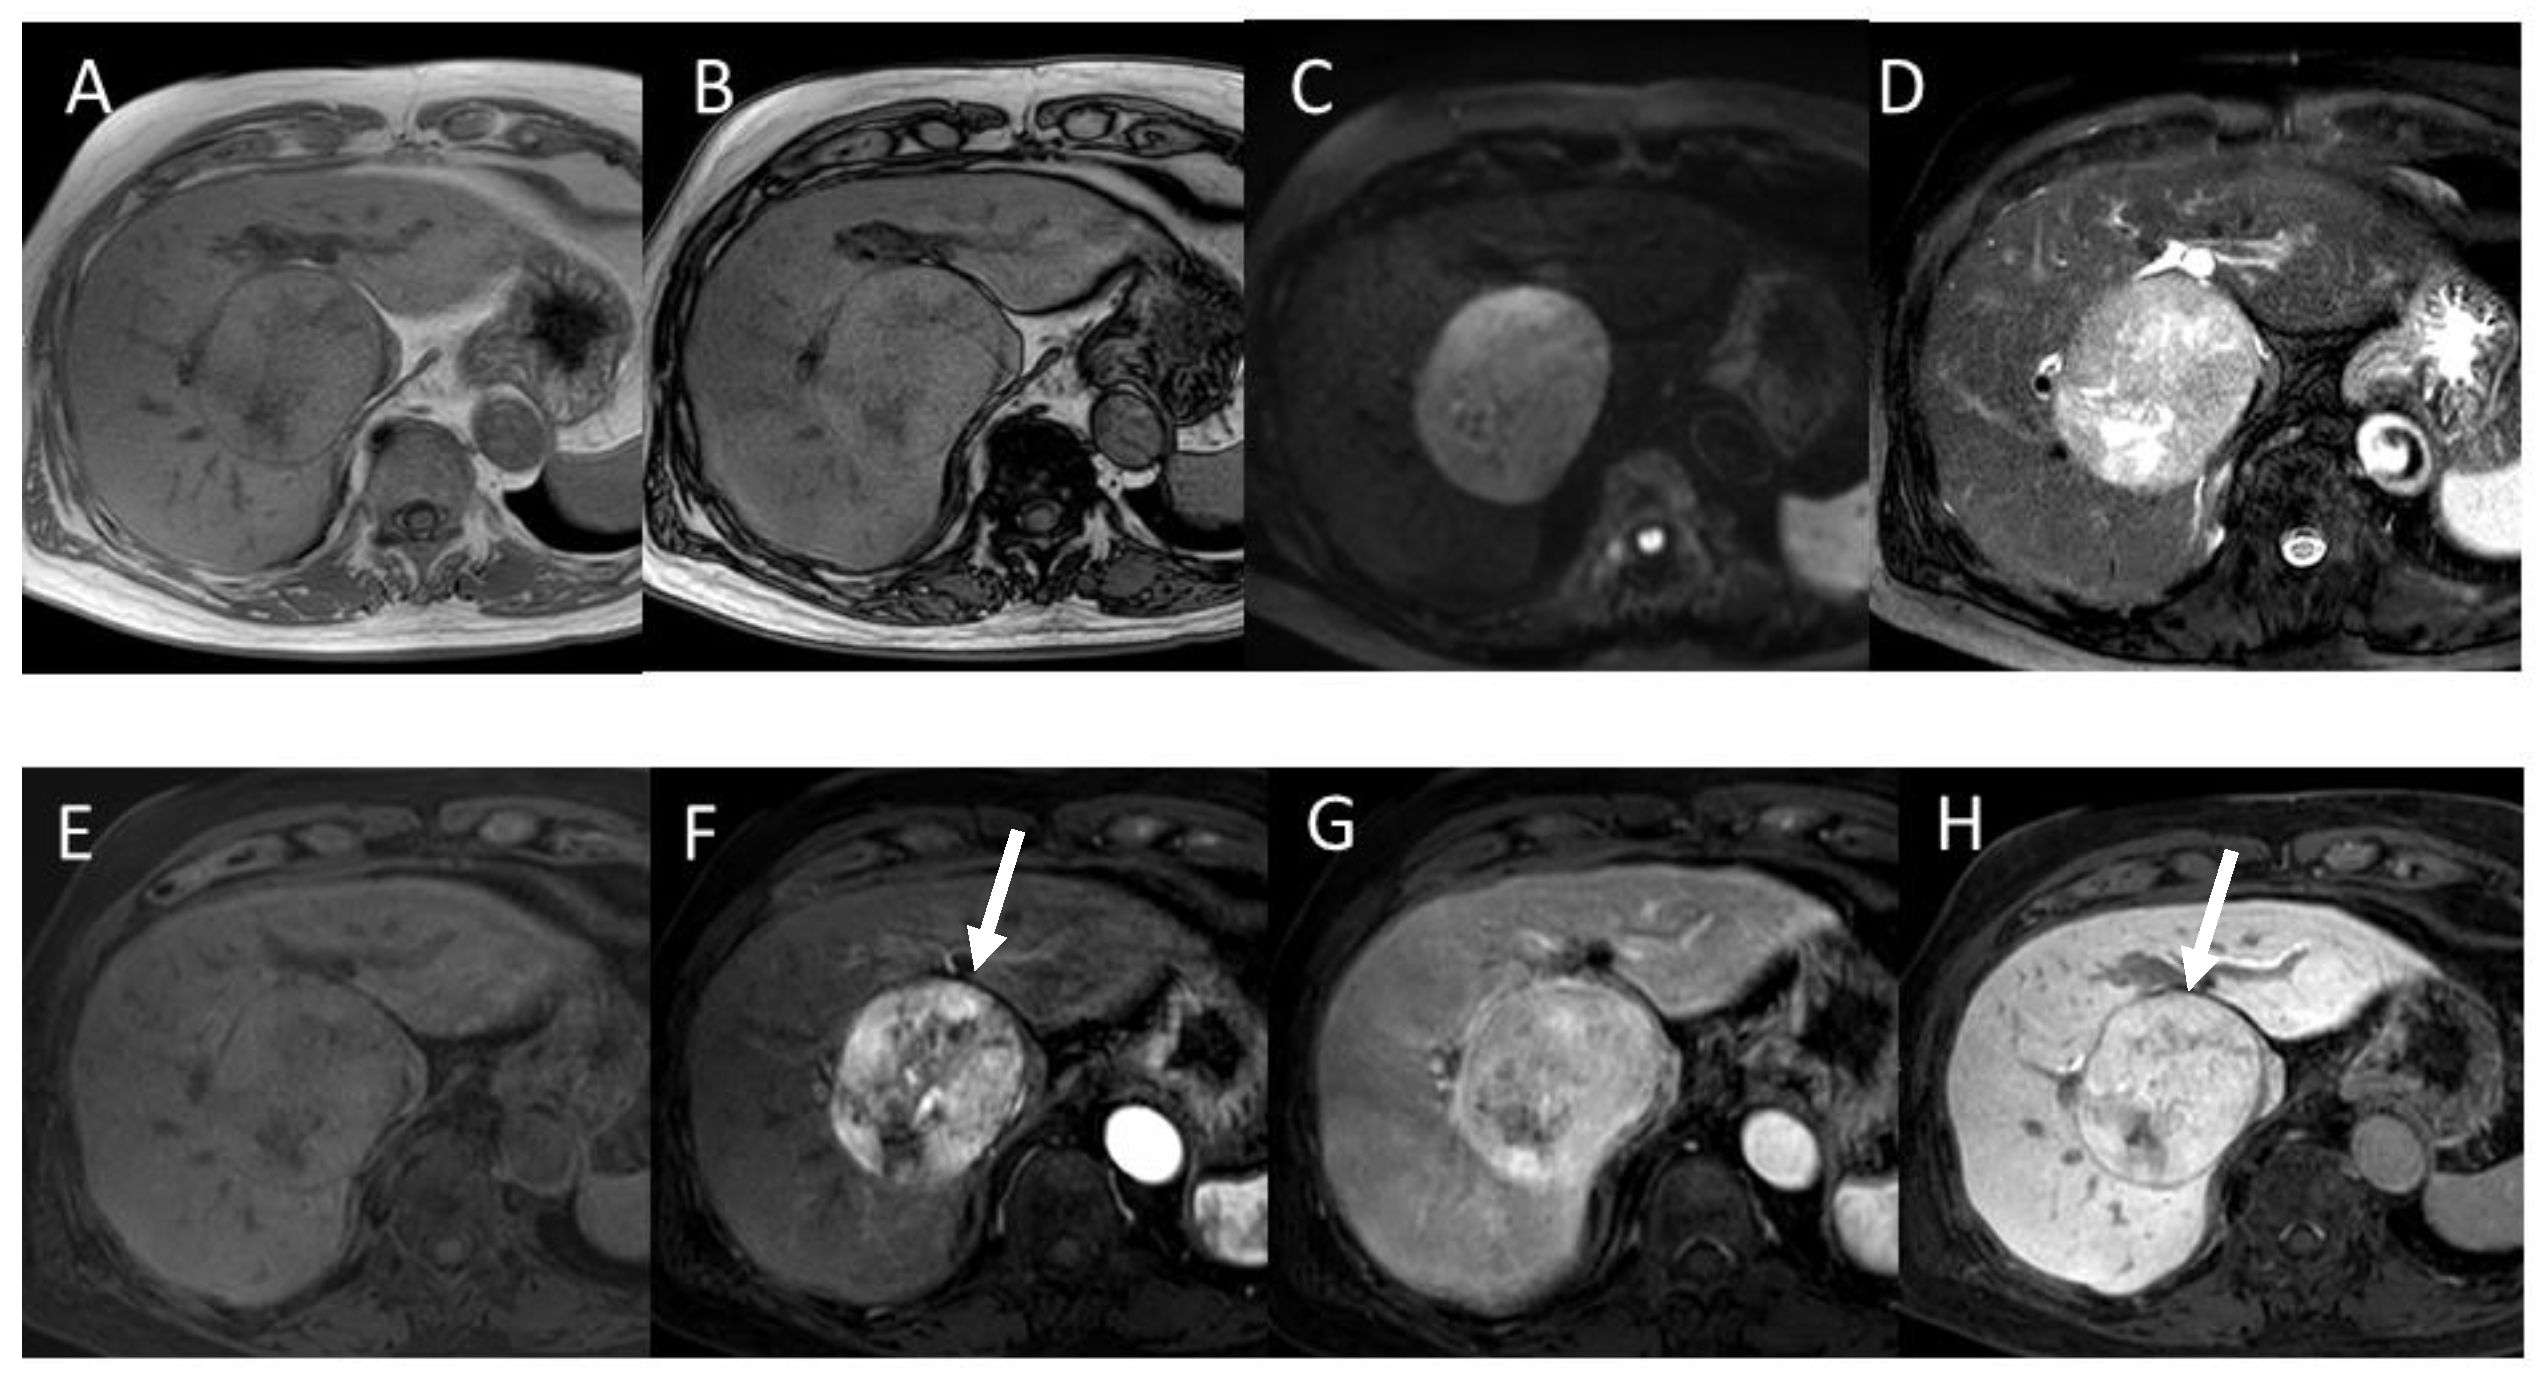

4.2. Early Hepatocellular Carcinoma (Early-HCC)

4.3. Well-Differentiated Hepatocellular Carcinoma (Well-HCC)